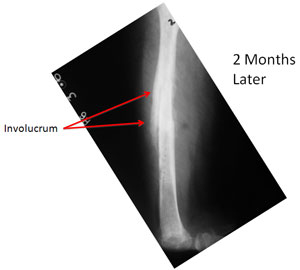

| The infection persisted and there is formation of new bone (Involucrum) around the dead necrotic bone (Sequestrum). |

At the time of presentation to us the Infected bone had weakened and broken (pathological fracture). The disuse osteoporosis of the bone is evident in the lower portion of the femur. The salt and pepper kind of appearance on the x-rays can represent a confusing picture of some kind of bone tumor. |